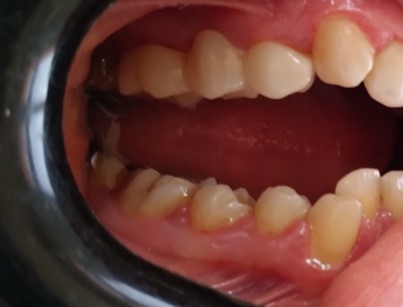

Before & After Gallery

Full E-MAX 4 crowns restoration